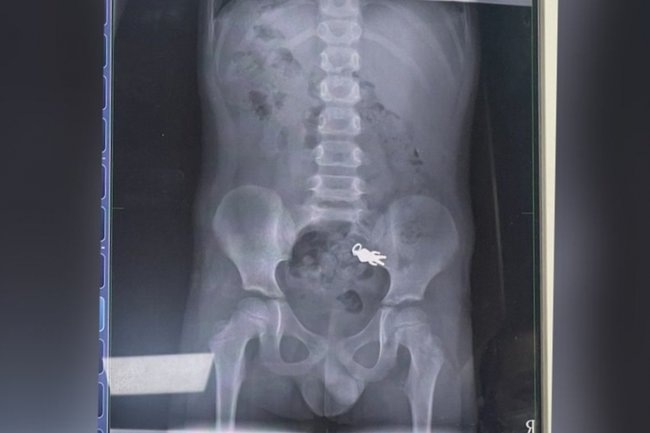

Узнав о произошедшем, родители немедленно отвезли сына в местную больницу. В медицинском учреждении мальчику сделали рентген, который подтвердил его слова. На тот момент фигурка Ультрамена уже переместилась в его тонкий кишечник.